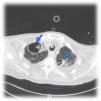

This is the case of a 76-year-old man with a past medical history of anticoagulated AF and mitral prolapse who presents to the hospital with clinical signs consistent with SARS-CoV-2-related pulmonary infection. The patient is diagnosed with bilateral pneumonia with atypical interstitial pattern suggestive of COVID-19 disease.

The patient presented a torpid evolution at the hospital conventional ward with respiratory gradient impairment and need for invasive respiratory support. As part of the medical therapy and with very established selection criteria, interstitial pneumonia with severe respiratory failure was found. The patient was treated with immunosuppressants, tocilizumab, and steroids. The patient showed a bronchial aspirate of Aspergillus fumigatus. The images reveal the presence of cavitatary lesions (aspergillosis) (Figs. 1–3).